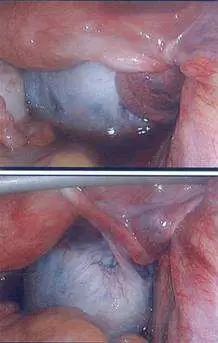

23 歲女性於近兩個月常感覺右下腹疼痛,此疼痛有時改變姿勢可改善症狀,今日則因疼痛加劇且合併有噁心嘔吐之情形就醫。理學檢查發現右下腹有壓痛及反彈痛之情形,經陰道指診發現子宮大小正常,但有觸壓疼痛的情形,同時子宮右邊有腫塊如鵝蛋大小,亦有觸壓疼痛的情形。超音波掃描發現右邊子宮附屬物有腫塊,大小約 7×8 公分。由於右下腹痛加劇,因此接受腹腔鏡檢查,腹腔鏡檢查發現有下圖之情形,依據圖示此患者最適合之診斷為:

腹腔鏡影像(上下兩格)顯示骨盆腔內有一大型白色/淡灰色光滑囊性腫塊,外觀飽滿、張力高,囊壁完整。腫塊周圍的骨盆腔組織(腹膜、輸卵管)呈粉紅至深紅色,顯示充血及缺血早期變化。腫塊表面光亮,未見化膿或穿孔跡象。下格圖片中可見金屬器械(抓鉗)正探觸腫塊,協助評估腫塊的扭轉程度。

此影像表現與卵巢腫瘤合併扭轉高度一致:

- 巨大囊性腫塊(7×8 cm)造成附屬器蒂部扭轉

- 扭轉導致靜脈及淋巴回流受阻,腫塊充血腫脹

- 腫塊呈蒼白色(缺氧缺血)而非暗紫色(尚未完全壞死)

- 腹腔鏡下可見扭轉的卵巢蒂(pedicle),為確診關鍵